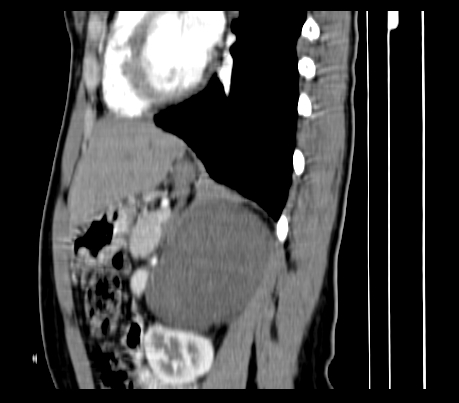

腹部平扫

动脉期